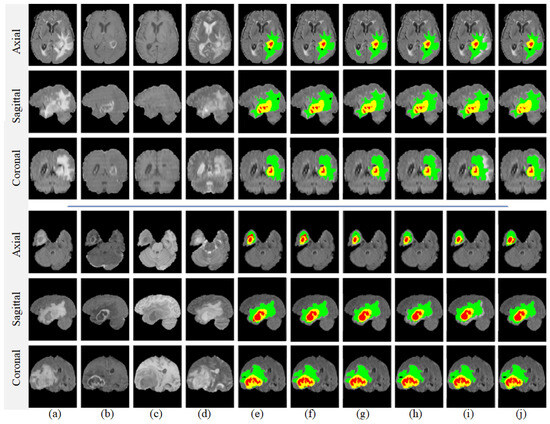

4.6. Qualitative Analysis